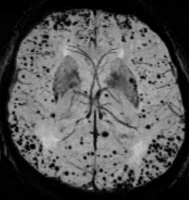

Abbildung 1: Signalauslöschungen durch Hämosiderinablagerungen durch zerebrale Mikroblutungen dargestellt durch eine Suszeptilitätsgewichtete Sequenz (SWI)

Darstellung

Signalauslöschung

suszeptilitätsgewichtete Sequenz

SWI

zerebrale Mikroblutung